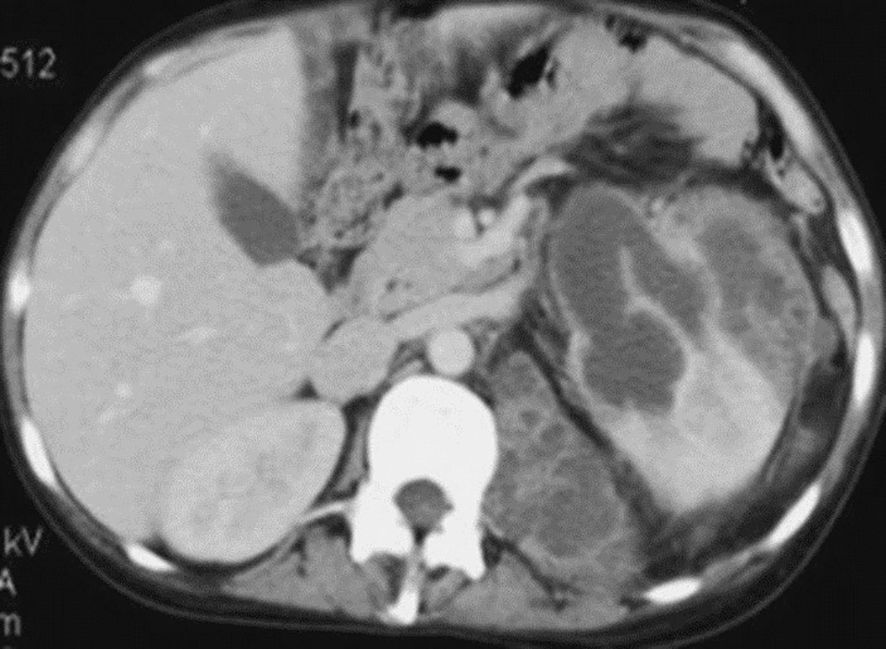

Background: Focal xanthogranulomatous pyelonephritis (XGP) is a rare chronic renal inflammatory disorder in children that often mimics renal neoplasms, complicating diagnosis and management. Methods: We describe two pediatric cases of focal XGP managed at our institution and provide a descriptive review of the literature (1975–2024), analyzing clinical presentation, imaging features, management strategies, and outcomes of this disease. Results: Case 1: A 2-year-old boy presented with a febrile right flank mass and systemic inflammation. CT Scan revealed an 80 mm multilocular renal mass. Surgical drainage and biopsy confirmed focal XGP, and targeted antibiotics led to complete resolution with preserved renal function at two-year follow-up. Case 2: A 10-year-old girl presented with a 40 mm left renal mass and systemic inflammatory signs. CT-guided aspiration and histopathology confirmed focal XGP. She was managed conservatively with intravenous and oral antibiotics, achieving complete resolution and normal renal function at seven-year follow-up. Literature review of 34 pediatric XGP cases (median age 11.1 years) showed that 53% were focal lesions. Conservative management with antibiotics, with or without drainage, succeeded in 64% of cases, and overall outcomes were favorable, with stable renal function and no reported mortality. Conclusion: This combined case series and descriptive literature review highlights that conservative, kidney-sparing management is a feasible and effective approach in selected pediatric focal XGP cases. Multicenter collaborations are needed to define standardized diagnostic and therapeutic protocols.